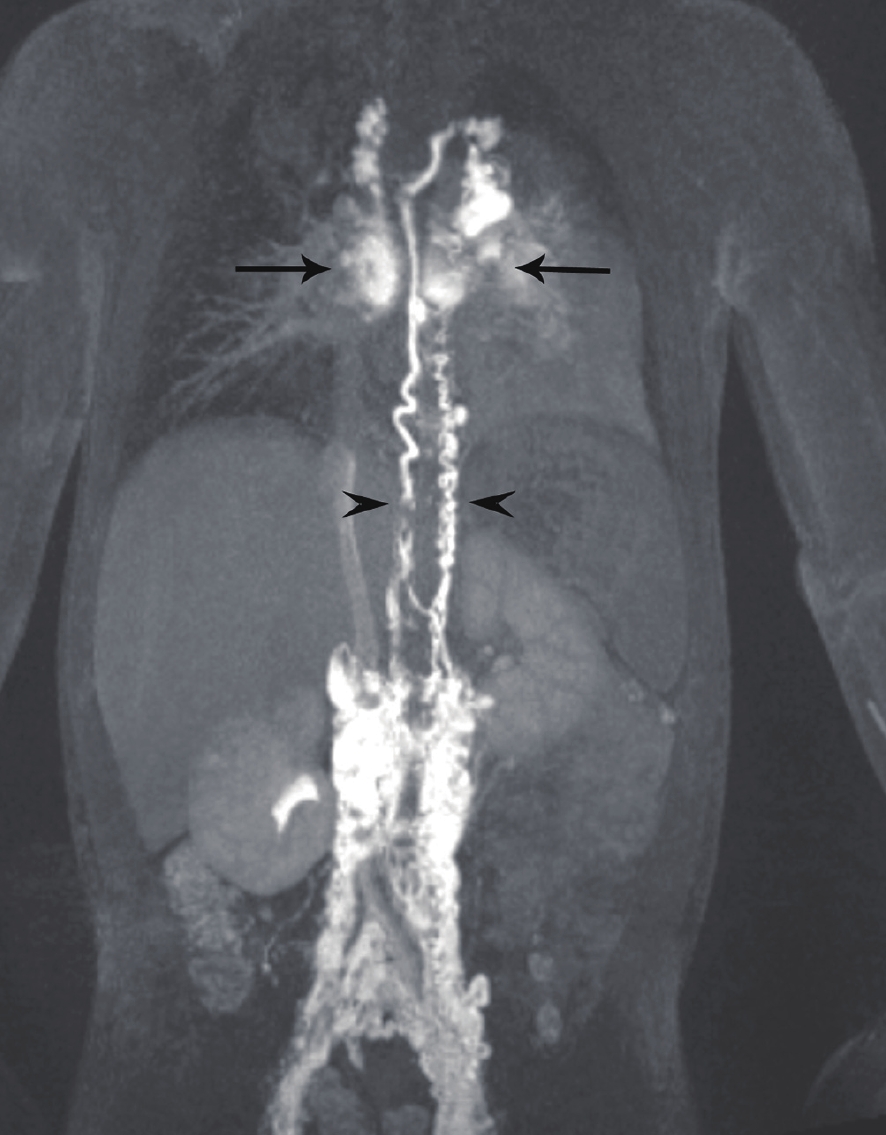

塑形性支气管炎(plastic bronchitis)可以继发于淋巴管发育异常,当中心静脉压升高如完全肺静脉异位引流、上腔静脉肺动脉连接手术后(fontan循环)导致胸部淋巴回流受阻,锁骨上区、纵隔、支气管周围及肺组织内淋巴管内压力增高而扩张,并使蛋白质含量较高的乳糜液漏入气道,形成支气管管型引起的气道阻塞。文献报道利用DCMRL检查可以证实乳糜液漏入气道,DCMRL表现为对比剂自肺门沿着肺部气管支气管树呈放射状分布,肺门区对比剂浓聚,且胸导管及中央淋巴系统迂曲扩张(图3),并可指导淋巴管异常的介入治疗[9-10]。

![]() 图 3 塑形性支气管炎患儿的动态增强磁共振淋巴管造影(DCMRL),双胸导管(短箭头)和异常肺淋巴流(长箭头)[9]Figure 3. DCMRL of the patient with PB, demonstrating double Thoracic duct (arrowheads) and abnormal pulmonary lymphatic flow (arrows)

图 3 塑形性支气管炎患儿的动态增强磁共振淋巴管造影(DCMRL),双胸导管(短箭头)和异常肺淋巴流(长箭头)[9]Figure 3. DCMRL of the patient with PB, demonstrating double Thoracic duct (arrowheads) and abnormal pulmonary lymphatic flow (arrows)2.2 淋巴管扩张症

图 3 塑形性支气管炎患儿的动态增强磁共振淋巴管造影(DCMRL),双胸导管(短箭头)和异常肺淋巴流(长箭头)[9]

Figure 3. DCMRL of the patient with PB, demonstrating double Thoracic duct (arrowheads) and abnormal pulmonary lymphatic flow (arrows)